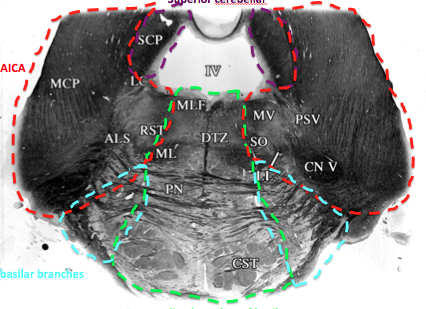

AICA

lateral part of middle pons until the rostral pons section

purple

superior cerebellar artery

supplies the superior cerebellar peduncle area throughout the pons

What supplies medial midbrain? for how long? (green)

paramedian branches of the basilar artery supply the midbrain all the way up

What supplies lateral portion of midbrain (blue)? for how long?

PCA

all the way up

als, ml, crus cerebri

what supplies top part of midbrain? for how long?

superior cerebellar, all the way up

supplies notably the inferior and superior colliclus

What can be damaged with AICA obstruction in the pons?

What supplies blood to the pons?

What features in the pons do the (paramedian) basilar branches supply blood to?

What features in the pons do the superior cerebellar artery supply blood to?

trochlear nerve

superior cerebellar peduncle

locus coeruleus

mesecenphalic trigem n.

some medial lemniscus

ALS

What features in the pons does AICA supply blood to?

middle cerebellar peduncle